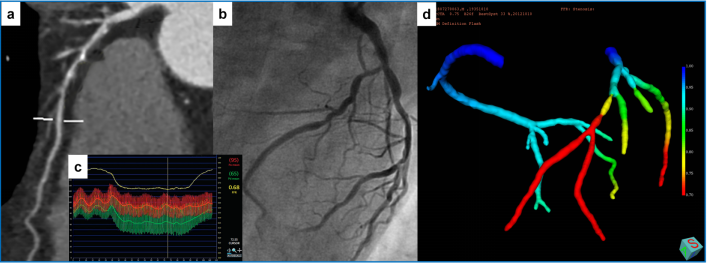

案例1:男性患者A,年龄60岁,诊断患有冠状动脉粥样硬化心脏病。快速FFR计算结果与有创FFR进行比较来说明FFRFAST的计算准确性。(A)CCTA多平面重格式化显示对角支(diagonal artery, D1)近端(a)和前降支(left anterior descending artery, LAD)中部阻塞性狭窄(红色箭头)(b),狭窄率分别为60%和80%;FFRFAST显示无明显缺血,LAD的计算值为0.83,D1的计算值为0.79(c);入侵式冠状动脉造影(Invasive coronary angiogram, ICA)也显示LAD和D1均无明显缺血,实测FFR值分别为0.84和0.82。(B)CCTA多平面重新格式化显示回旋支(left circumflex artery, LCX)中部阻塞性狭窄(红色箭头),狭窄率80%(a);FFRFAST显示出明显的局部缺血,计算值为0.73(b);ICA同样显示缺血,实测FFR值为0.75。

案例2:男性患者B,年龄77岁,诊断患有冠状动脉粥样硬化心脏病。快速FFR计算结果与导丝FFR进行比较来说明FFRFAST的计算准确性。CCTA多平面重格式化显示LAD中段弥漫性病变(a),最严重狭窄率为75%;ICA显示狭窄明显,导丝测量LAD远端FFR为0.6(b, c);FFRFAST也显示出明显的心肌缺血,计算值为0.61(d)。

案例3:男性患者C,年龄60岁,诊断患有冠状动脉粥样硬化心脏病。快速FFR计算结果与有创FFR进行比较来说明FFRFAST的计算准确性。(A)CCTA多平面重格式化显示回旋支近段动脉粥样硬化,钝缘支中段90%狭窄(a);ICA显示狭窄明显,导丝测量LCX远端FFR为0.68(b, c);FFRFAST也显示出明显的心肌缺血缺血,FFR计算值为0.7(d)。